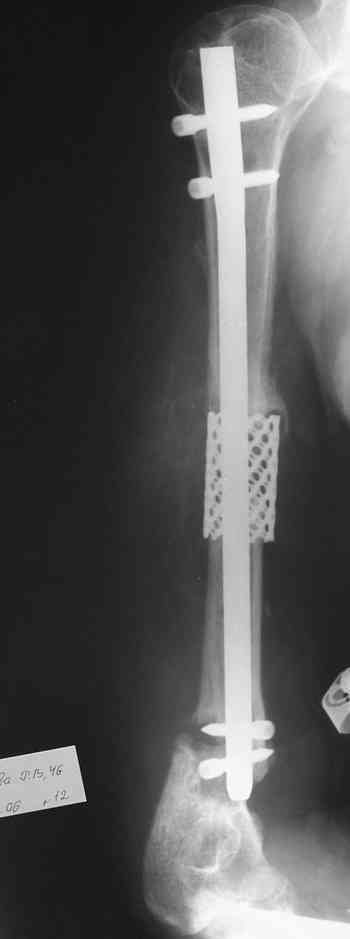

Такие надмыщелковые переломы в изолированном виде у нас в последние годы обычно фиксируются плоским титановым стержнем a la Зверев-Ключевский антеградно. Но тут еще и вышележащие проблемы.

Наверно, можно пойти на укорочение, убрав металлический цилиндр, не такой уж большой дефект. Снимки в чем-то похожего пациента прилагаю - тоже несращение диафиза после многократных операций, и надмыщелковый свежий перелом (случился после удаления обломка стержня аппарата).